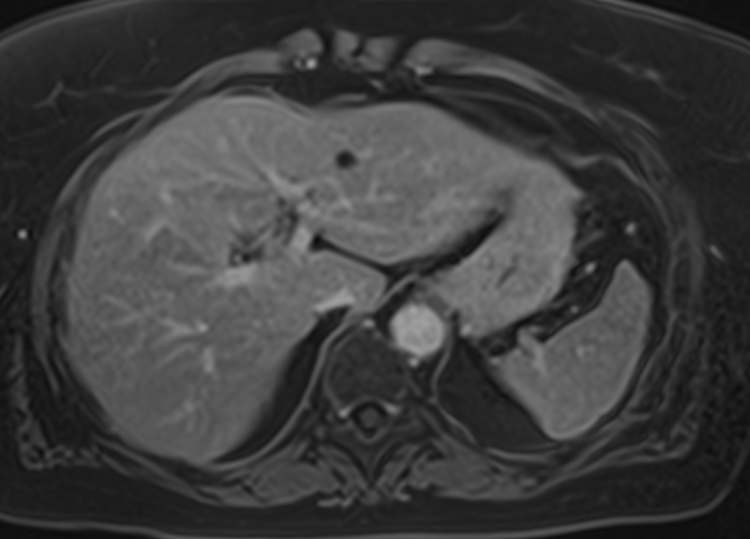

В клинике «Доступная медицина» МР томография проводится на новейшем высокопольном томографе экспертного класса TOSHIBA VANTAGE TITAN 1,5 Тесла. Высокая индукция магнитного поля обеспечивает повышенную четкость изображений при проведении обзорной МРТ брюшной полости, что гарантирует точность и эффективность диагностики заболеваний печени, желчного пузыря, поджелудочной железы и селезенки. Аппарат послойно сканирует исследуемую область с шагом от 1 мм в различных плоскостях, затем трансформирует результаты в трехмерные изображения превосходного качества. Для уточнения характера патологических изменений одного из органов назначается прицельная МР томография данного органа.

Для расширения возможностей диагностики, при необходимости уточнения характера патологических изменений применяется контрастное усиление. Для этого в вену вводится контрастный препарат, содержащий металл гадолиний (Магневист, Гадовист и др). Препарат фиксируется в очагах поражения, позволяя диагностировать их при минимальных размерах, что бывает особенно важно в диагностике опухолей.

- Доброкачественные образования (кисты, гемангиомы) и злокачественные опухоли органов брюшной полости (первичные опухолевые очаги и метастатические поражения, в том числе, брюшины).

- Заболевания печени (жировая инфильтрация печени, гепатиты, цирроз и др).

- Заболевания желчного пузыря и желчевыводящих протоков, поджелудочной железы (желчекаменная болезнь, холецистит, панкреатит и др).